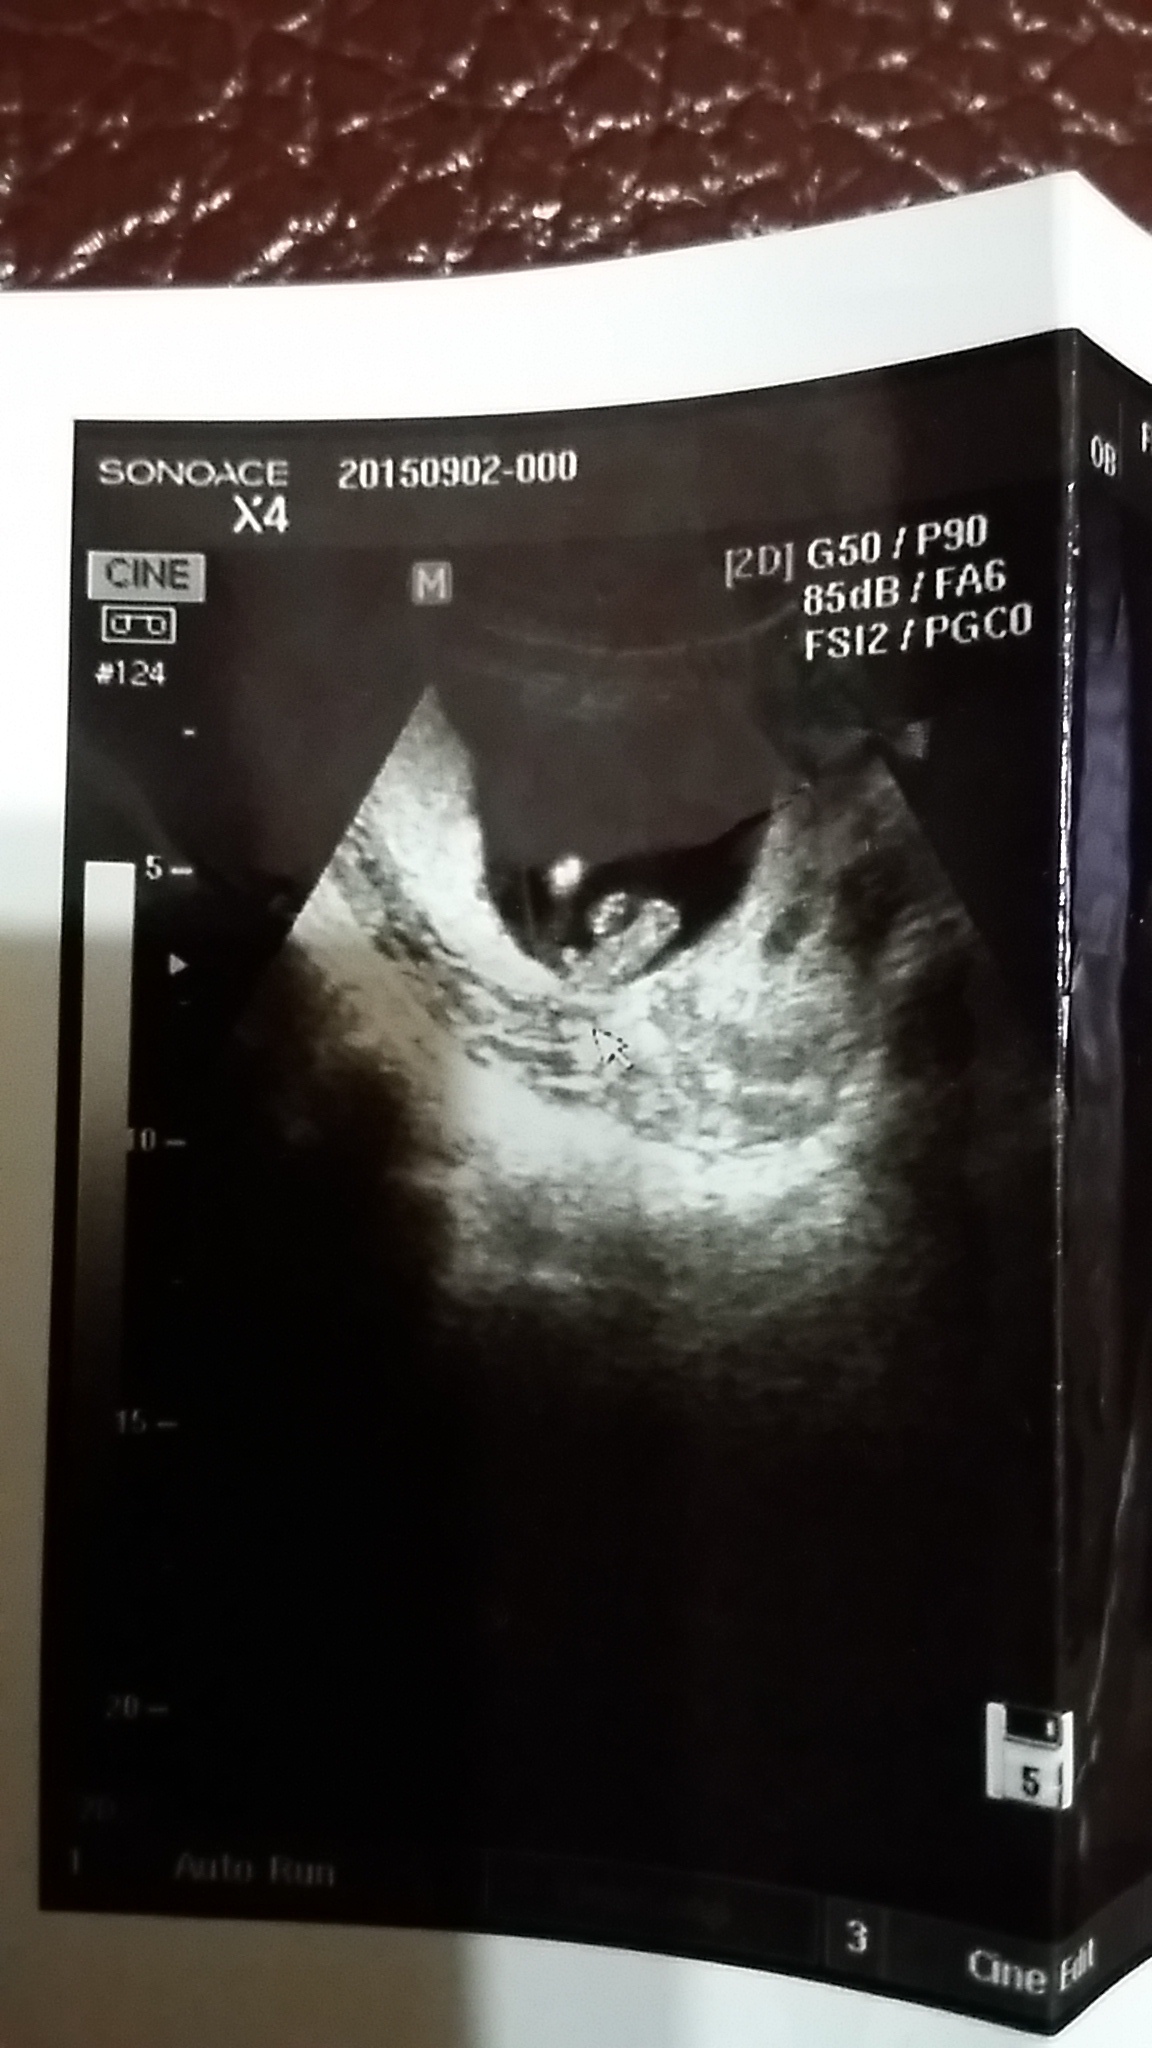

這張是快14週的超音波照片,看的出是男還是女嗎?

醫生說屁股中間小小的凸白點,疑似男的。